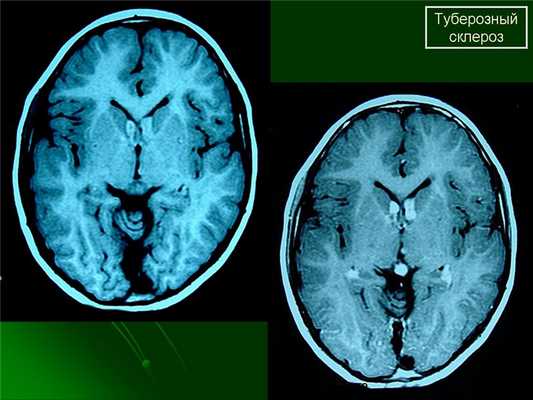

Субэпиндемальные узлы и корковые туберсы на МРТ

Для детей раннего возраста, на еще незавершенных процессов миелинизации наиболее типичными изменили является линейные очаги на Т2ВИ выявляемые по ходу миграционных путей больших полушарий головного мозга. Эти изменения могут сочетаться с кортикальными и субкортикальными очагами ( туберами ), так и быть единственным проявлениям при МРТ исследовании. Наличие кортикальных и субкортикальных туберов типично для всех возрастных групп пациентов. В их проекции могут формироваться кисты, так же они могут быть частично или полностью кальцинированы. Их размеры и количество варьируется индивидуально для каждого больного.

Наиболее типичная локализация большие полушария головного мозга, однако у 15% пациентов туберы могут располагаться в мозжечке. Туберы представляют собой глионейрональные гамартомы и состоят из дезорганизованной клеточной ткани белого вещества.

При подозрении на эту болезнь обязательно следует проводить МРТ головного мозга. При этом в головном мозге выявляются характерные МРТ-признаки туберозного склероза: корковые и подкорковые узлы (туберсы), субэпендимальные узелки (гамартомы), а также различные изменения белого вещества - очаговые и кистозные.

МРТ головного мозга при туберозном склерозе. Участки изменения МР-сигнала неправильной формы в коре и подкорковом белом веществе — так называемые корковые туберсы.